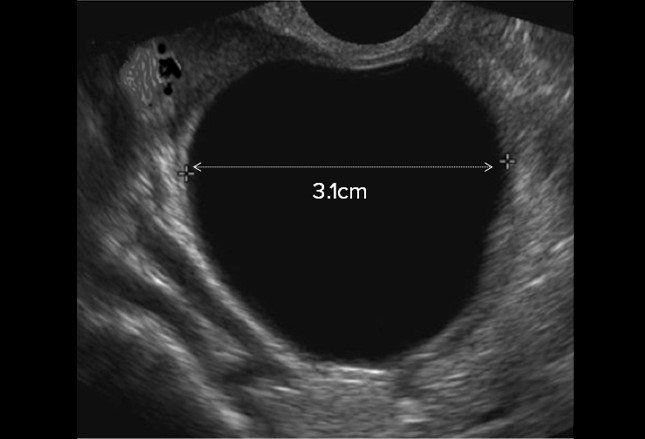

• Ovarian Cyst

Ovarian cysts

3. Ovarian cysts